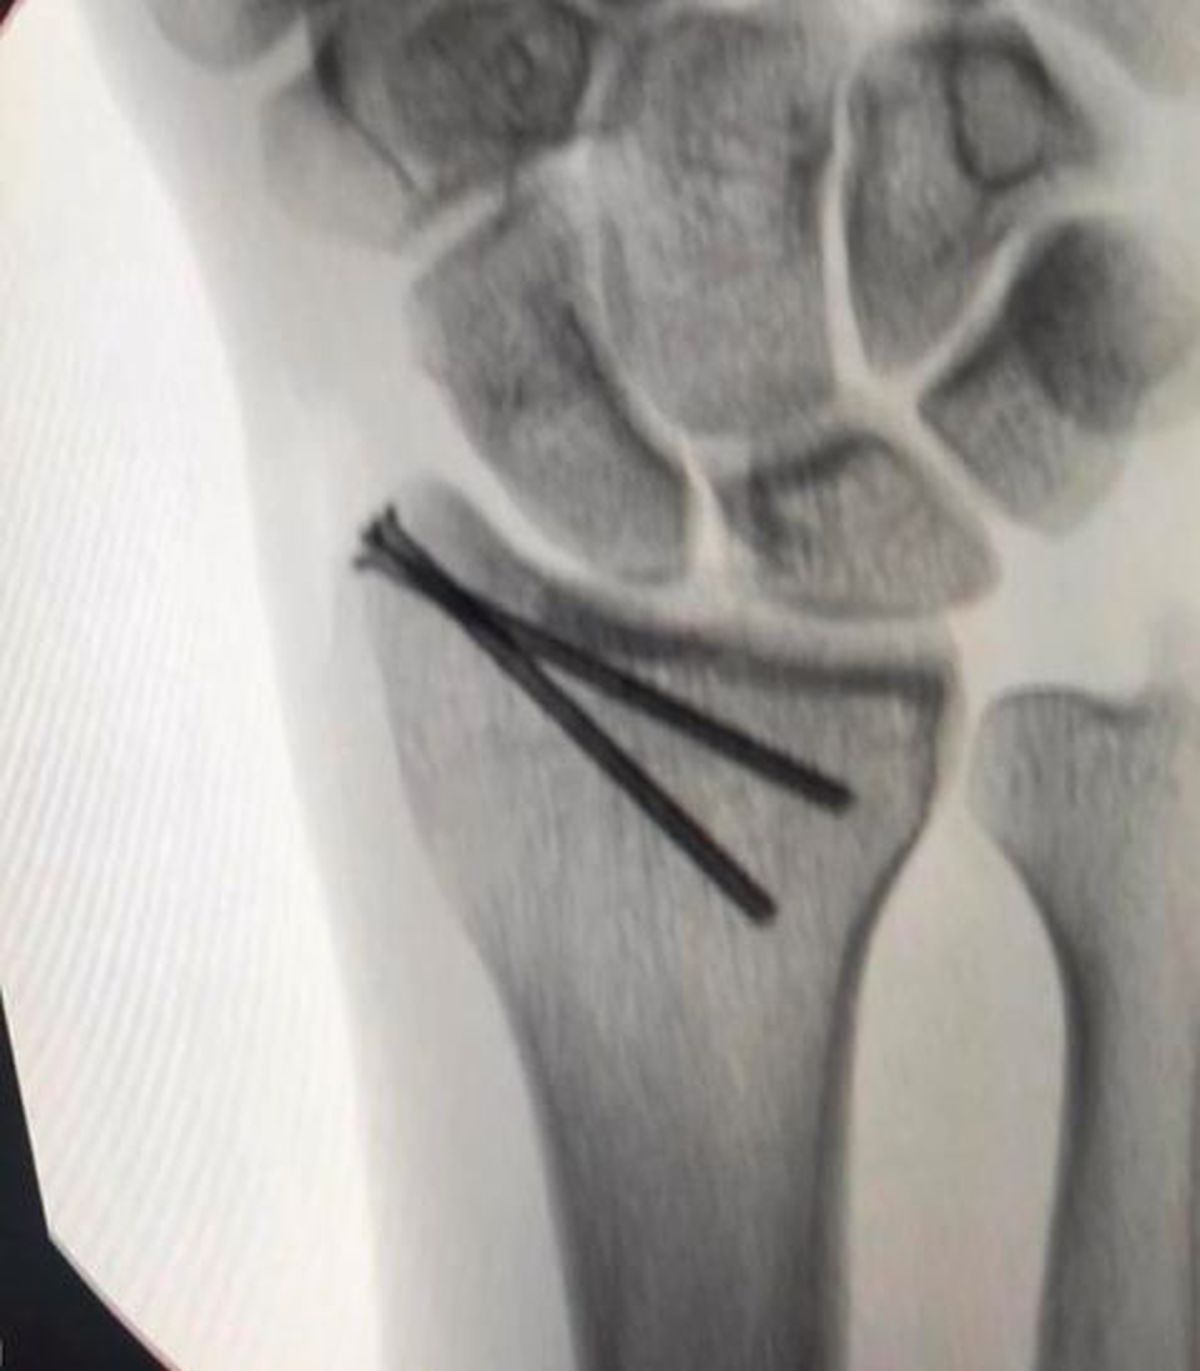

Foto 3/34